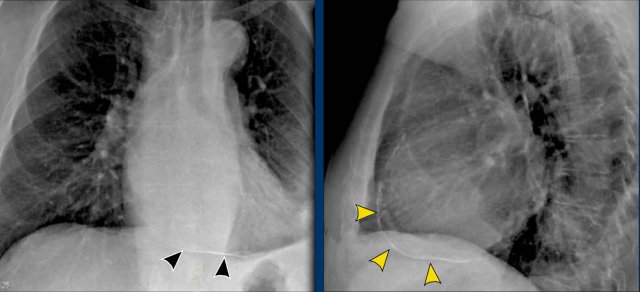

Bochdalek hernia Bochdalek hernia

Congenital Diaphragmatic Hernias

Bochdalek Hernia

• A Bochdalek hernia is a common incidental finding in adults and results from a posterior diaphragmatic defect(arrows).

• It typically contains retroperitoneal fat, is asymptomatic, and discovered incidentally.

• In rare cases, abdominal organs may herniate into the thorax.

• In neonates, large Bochdalek hernias may lead to pulmonary hypoplasia, which can be life-threatening.

Morgagni Hernia

• A Morgagni hernia is a less common congenital diaphragmatic hernia.

• It is located anteriorly, often presenting as a right-sided retrosternal mass.

• Like Bochdalek hernias, it may be asymptomatic or contain herniated abdominal contents.